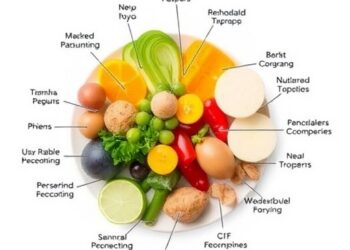

Dietary Inflammation Linked to Type 1 Diabetes Profiles

In a groundbreaking study that sheds new light on the complex relationships between diet, inflammation, and metabolic health in young...